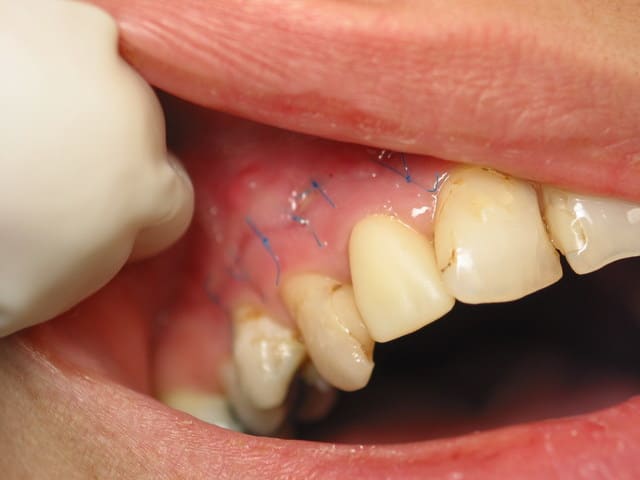

bref sutures, compression, prescription, glace et ciao.

Pour athos : lambeau de pleine épaisseur biseauté à 3 mm du sulcus afin de préserver l'esthetique des couronnes. Lors du décollage, il apparait que la corticale externe a été soufflée complètement et qu'il n'en subsiste que des petits fragments "coquille d'oeuf" noyés dans un épais tissus fibreux réactionnel.

photo : pas d ecarteurs c trop tot encore. Notez la propreté des fils a propylene en 6/0